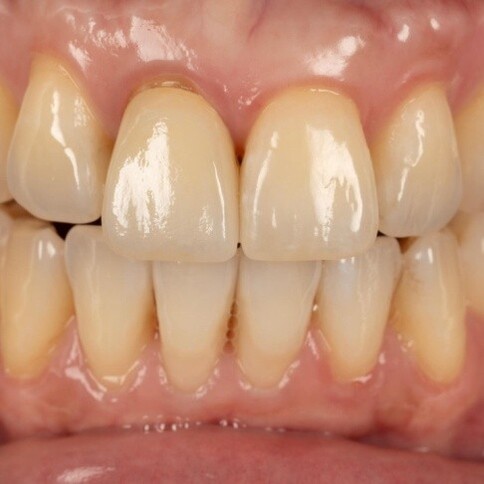

當您只有「單顆」門牙受損時,挑戰在於模仿隔壁那顆「天生的牙」。我們利用全瓷冠的高透光性創造視覺平衡,避免做出一顆看起來很新卻很突兀的假牙。

Case 1:舊假牙死白換新,牙肉回彈跡象。